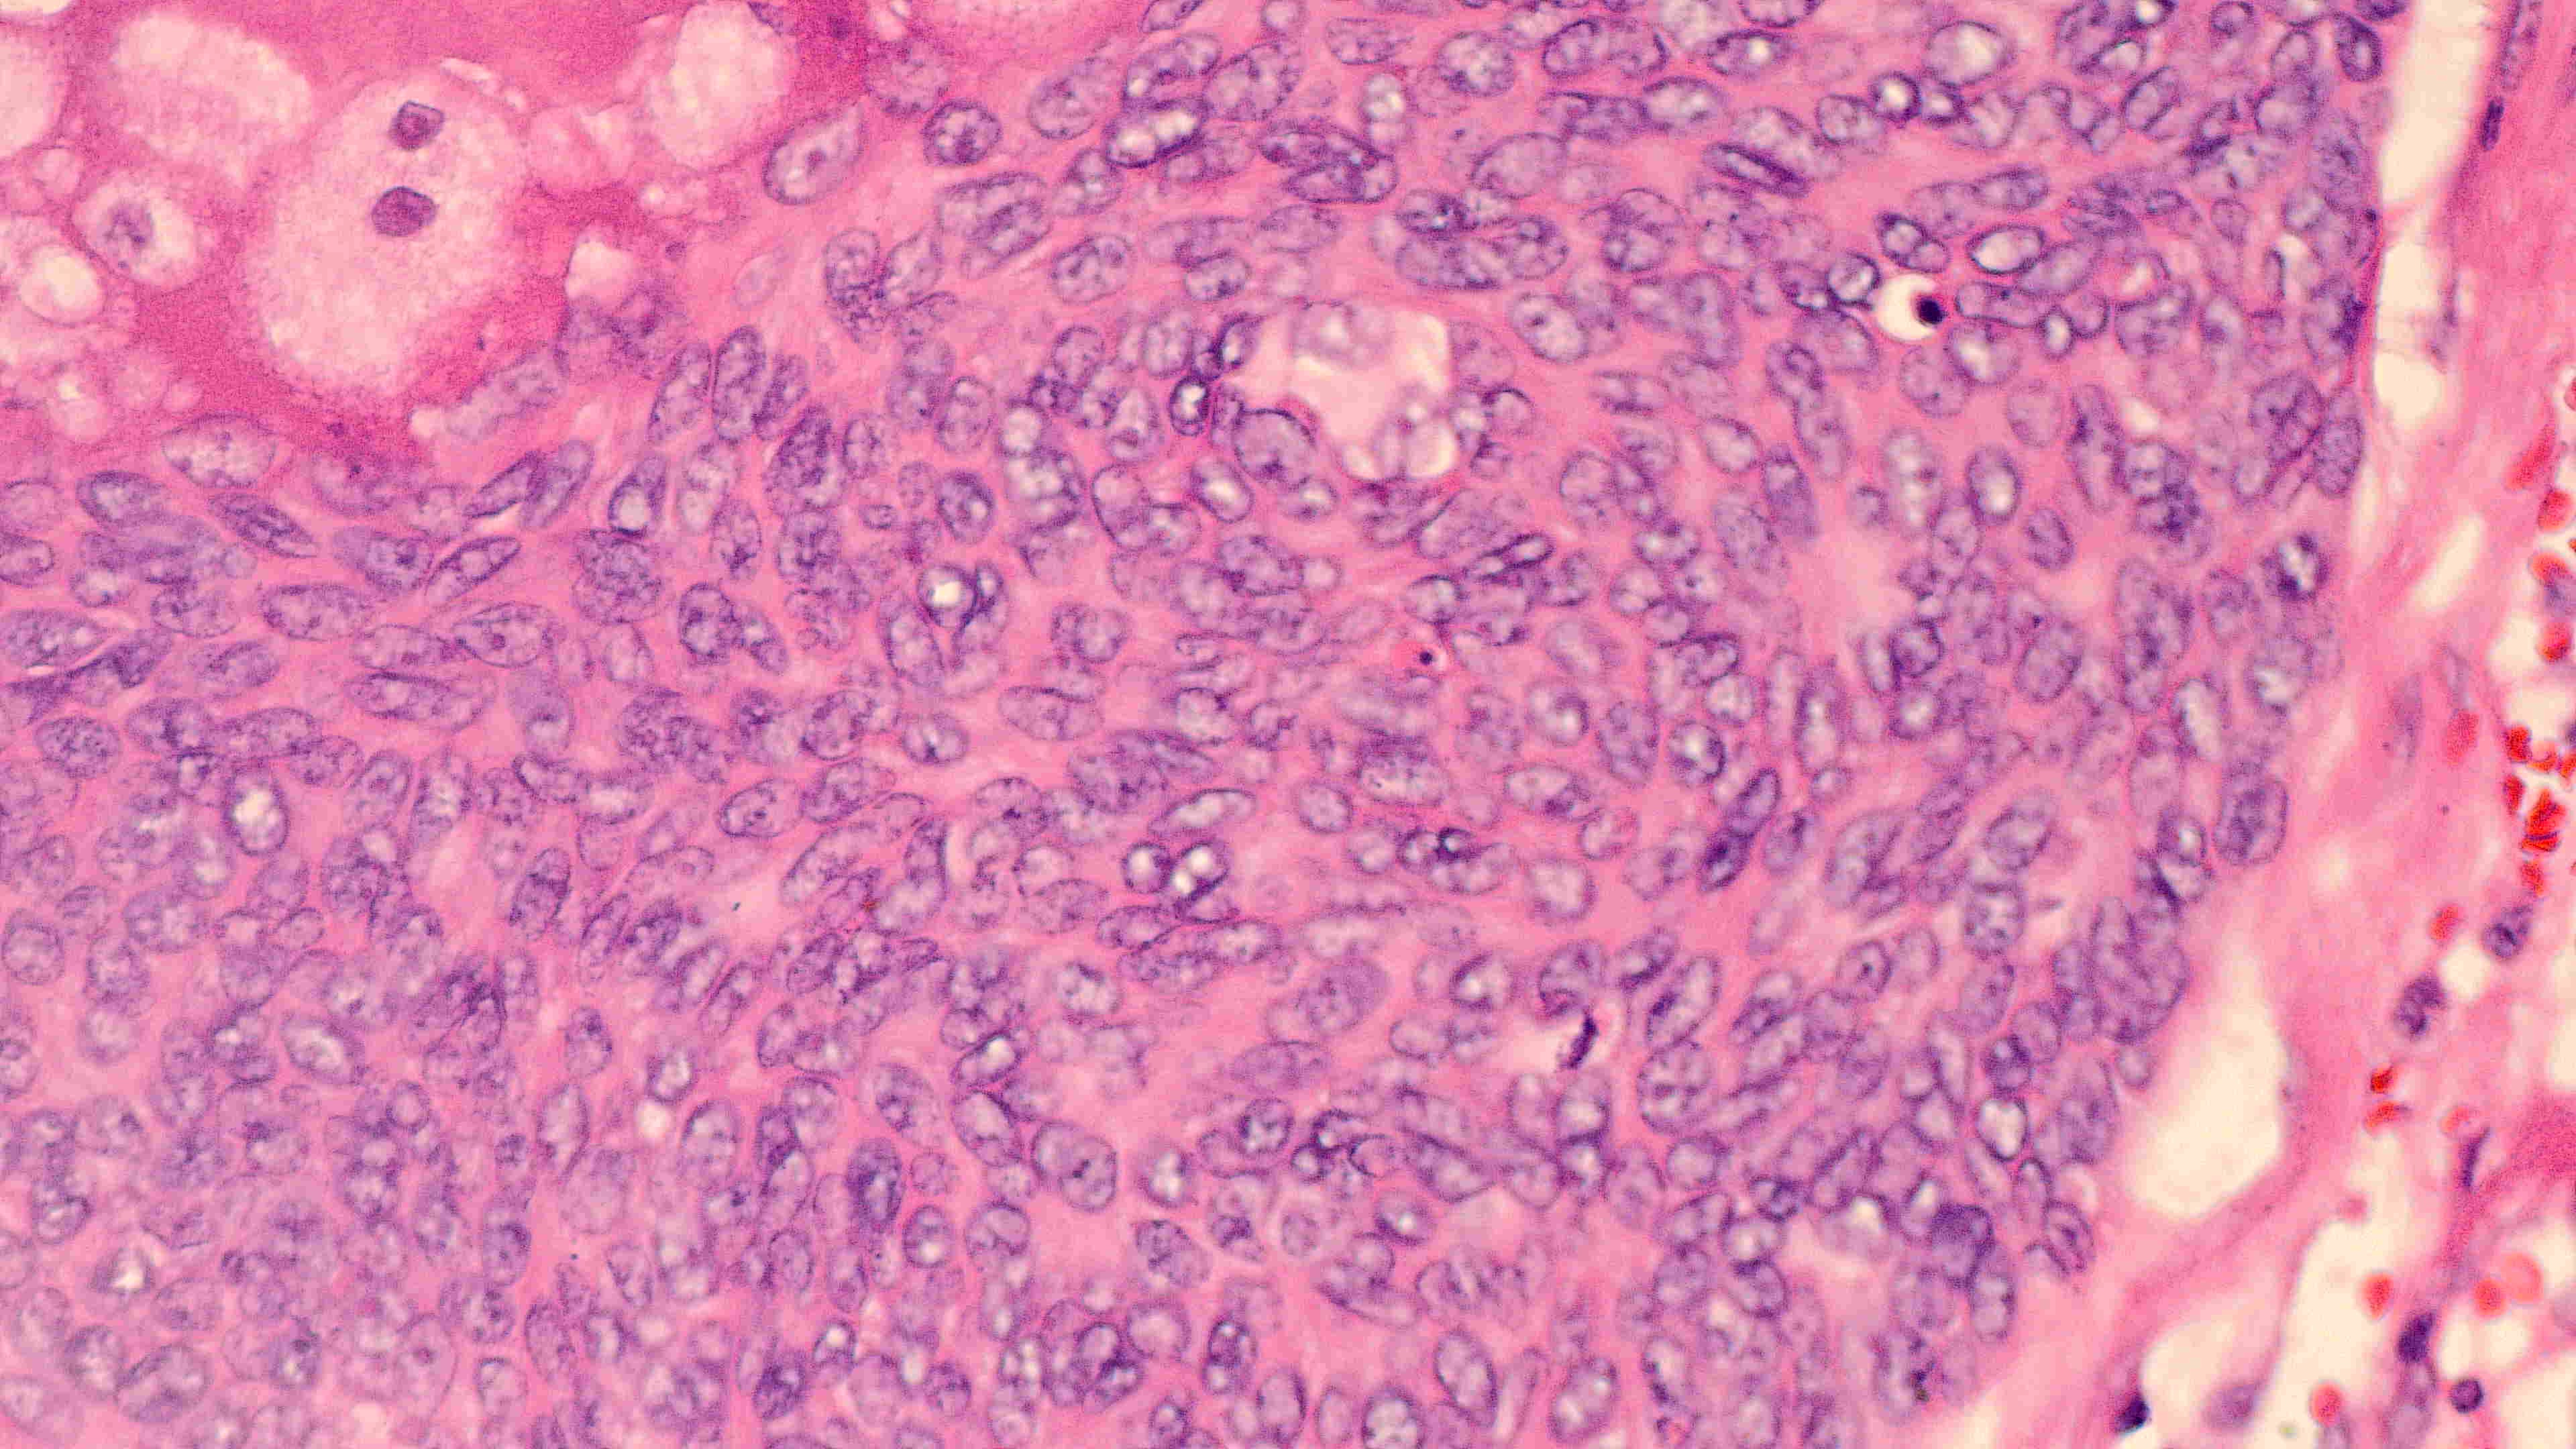

下巴肿物

带皮不规则组织3*3*2cm,切面灰白灰褐实性质软

会诊结果:小汗腺汗孔癌